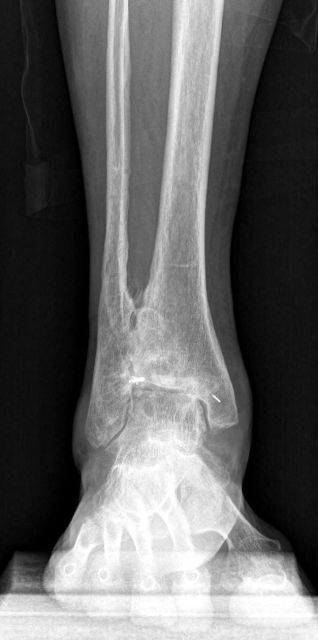

Bei Patienten mit schwerer Degeneration des Sprunggelenks (Arthrose) sind typische Symptome Schmerzen, fehlende Stabilität, Reduktion der Gehfähigkeit, Verschlechterung des Bewegungsumfanges des Sprunggelenks und oft auch zunehmende Fehlstellung des gesamten Fußes (X-Bein, O-Beinfehlstellung). Bei leichteren Formen leiden die Patienten unter Belastungsschmerzen, während bei fortgeschrittener Arthrose die Schmerzen auch in Ruhe auftreten.

OSG-TP vorher-nachher